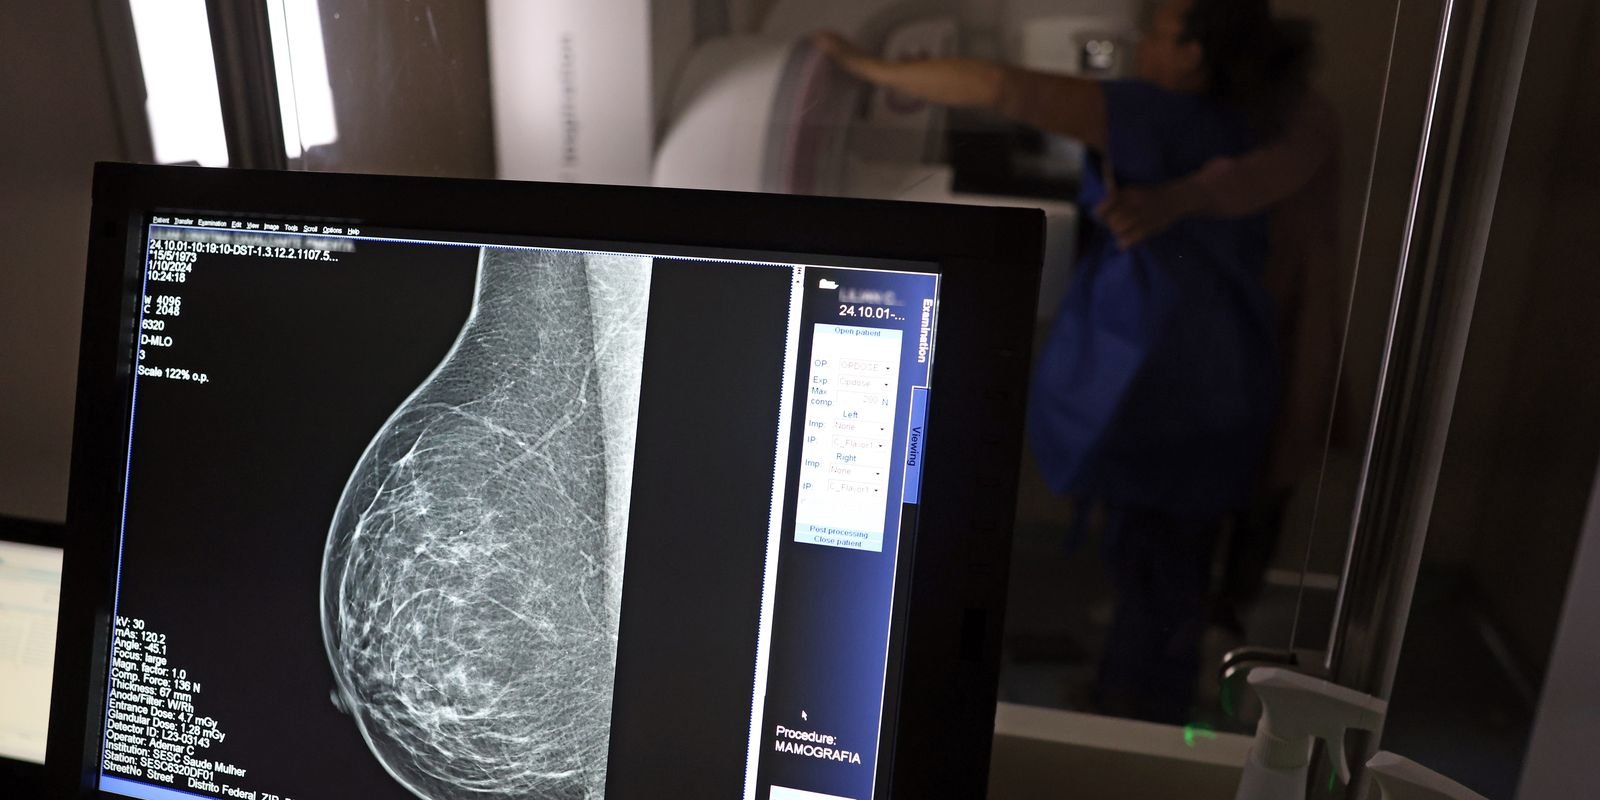

Falta de acesso a mamógrafos limita prevenção do câncer de mama

No mês de conscientização sobre o câncer de mama, um relatório destaca a importância de acesso igualitário ao rastreamento e tratamento da doença. Segundo o Atlas da Radiologia no Brasil, do Colégio Brasileiro de Radiologia e Diagnóstico por Imagem (CBR), o acesso aos mamógrafos ainda é um desafio.

Em setembro, o Ministério da Saúde ampliou as diretrizes de rastreamento, recomendando que mulheres entre 40 e 49 anos realizem mamografias, mesmo sem sintomas. De acordo com o Instituto Nacional do Câncer (Imca), mais de 73 mil mulheres recebem o diagnóstico de câncer de mama anualmente no Brasil.

“O que é efetivo na redução da mortalidade é você descobrir o tumor antes de ter sintoma clínico. Quanto menor o tumor, melhor para a gente descobrir o tratamento e maior a chance de cura. E a gente só consegue fazer isso com exames de imagem”, diz Ivie.

Ela explica que no caso de diagnóstico de um câncer de mama com menos de 1 cm, a chance de cura é de 95% em cinco anos, independentemente se ele é do tipo mais agressivo. “E esses tumores só vão ser detectados na mamografia. Essas pessoas que têm que ir fazer mamografia são mulheres saudáveis. Não são mulheres doentes”, acrescenta.